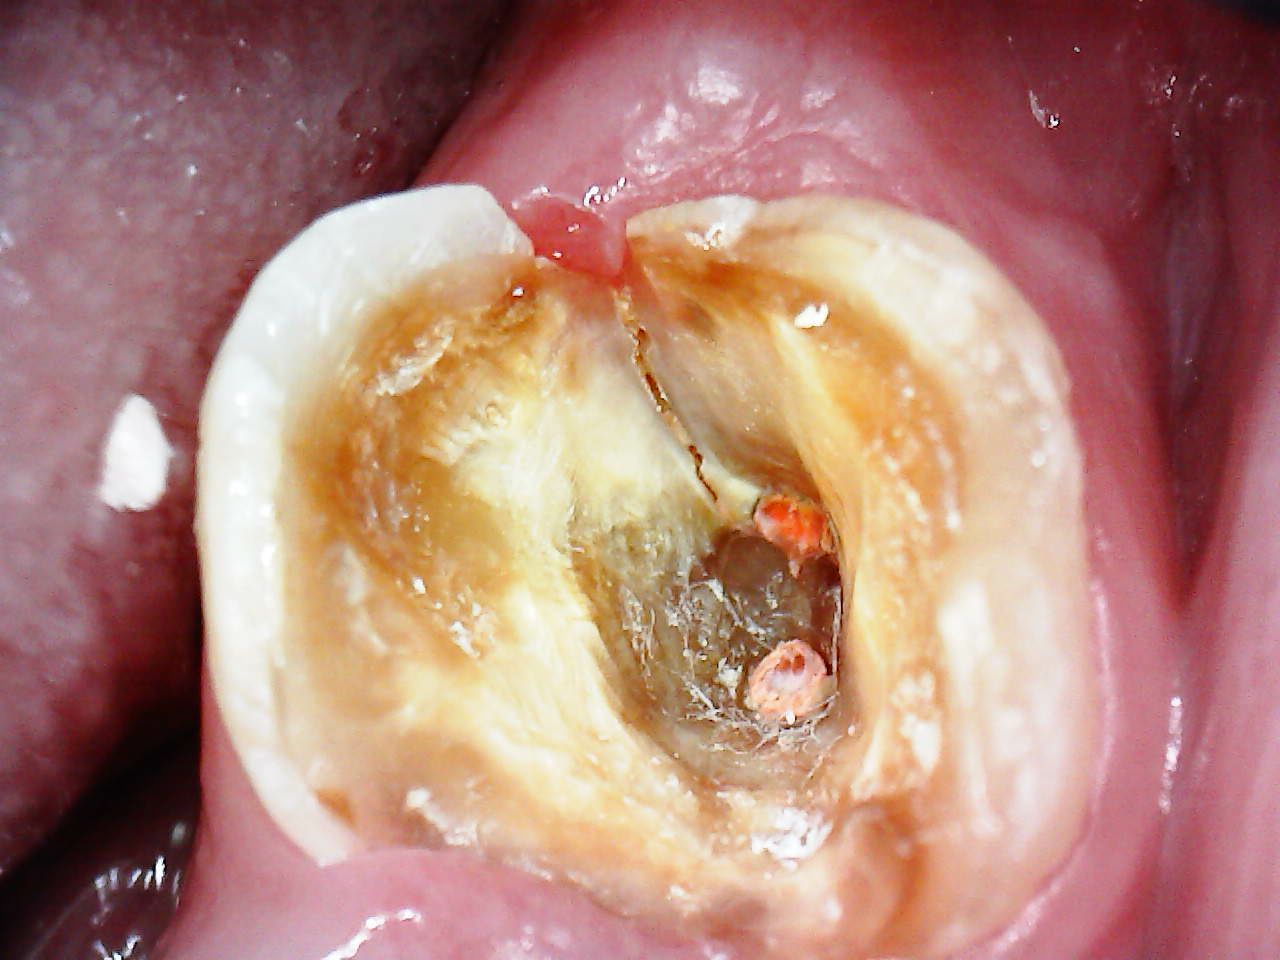

1. Enxergar o que o olho humano não vê

Trincas, fraturas e infiltrações ficam extremamente evidentes com a ampliação da SkyCam.

Exemplos reais de uso da SkyCam na Endodontia

Detalhamento preciso de microestruturas

Imagens altamente nítidas para avaliar a verdadeira extensão da lesão.

Dor sem causa aparente? A SkyCam revela trincas e infiltrações invisíveis.